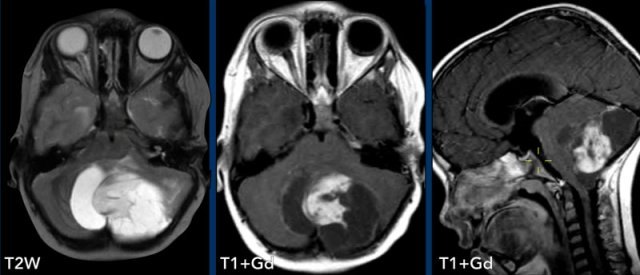

These images are of a 9-year old child who presented with headache.

Images

there is a large cystic posterior fossa mass with compression and

obstruction of the fourth ventricle and brainstem.

A solid contrast enhancing

nodule is present, as well as enhancement of the cyst wall.

Conclusion

Most likely diagnosis at this age is a pilocytic astrocytoma

These images are of a 3-year old child who also presented with headache.

There are two important findings.

Take a closer look at the images and then continue reading.

Large cyst with enhancing nodule in the posterior fossa..

Notice that the wall of the cyst enhances.

The nodule is not located on the pial side (inner part of the meninges) unlike in a hemangioblastoma.

Most likely diagnosis at this age is a pilocytic astrocytoma.

The enhancing wall is part of the tumor and needs to be resected.